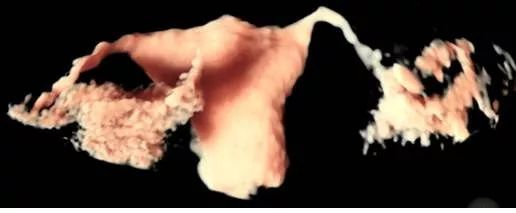

而輸卵管超聲造影,麻醉醫生會在術前給予靜脈麻醉,然后在B超監測下從子宮造影管里注射造影劑,動態地觀察造影劑在宮腔輸卵管里的情況。操作簡便,圖像清晰,無創安全,副作用少,準確性更高,不會受到射線輻射,可在當月嘗試懷孕,建議一個月后試孕。

無痛子宮輸卵管4D超聲造影檢查

精確評估輸卵管功能

設備先進:引進美國GE Voluson E8彩色多普勒超聲造影儀,可明確輸卵管是否通暢及阻塞部位,還可對子宮、卵巢及盆腔內情況做出全面診斷,圖像清晰,實時動態,診斷準確率高。